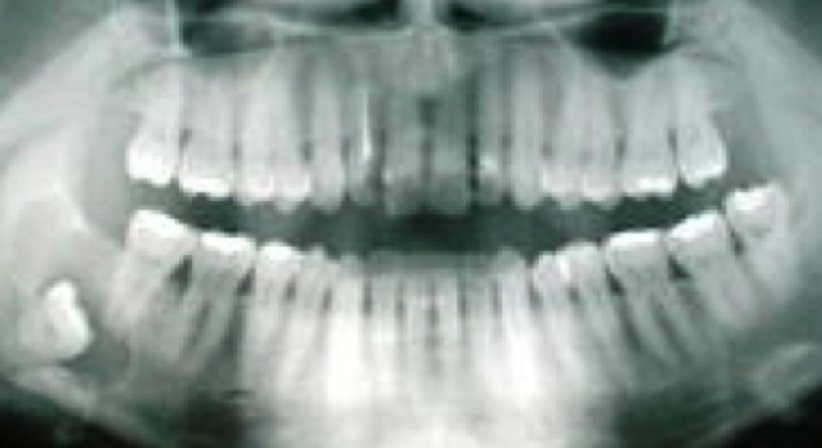

Bei größeren Zysten kann es zu Auftreibungen im Mundvorhof oder gar äußerlich im Kieferwinkelbereich kommen. Auf Druck kann man eventuell ein pergamentartiges Knistern wahrnehmen, wenn die oft dünne äußere Knochenlamelle zerbricht. Wegen ihrer Schmerzlosigkeit sind odontogene Zysten oft Nebenbefunde bei Röntgenaufnahmen Zysten können auf Grund ihrer Verdrängung während ihres Wachstums Zähne verschieben oder kippen lassen. Es kann auch zu Wurzelresorptionen kommen, die wiederum zur Zahnlockerung (bis hin zum Zahnverlust) führen können.